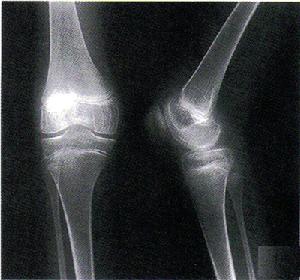

白塞病綜合徵-關節炎其它輔助檢查:

1.X線檢查 關節脊柱X線片可見關節腫脹,極少數可出現關節變形及強直性脊柱炎的表現如纖維性和骨性強直。肺部受累時X線片可見肺部陰影,肺動脈病變可出現肺動脈高壓症的X線表現。